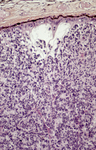

Histopathology of retinoblastoma. This image demonstrates the classical features of retinoblastoma, including densely packed, small, round tumor cells with hyperchromatic nuclei and scant cytoplasm, arranged in sheets. The absence of Flexner-Wintersteiner rosettes in this specimen does not preclude the diagnosis, as their presence is not obligatory. These histopathological features are typical of this aggressive retinal tumor and provide critical information for diagnosis, staging, and prognosis

PR J. L. Kemeny, ISM/Science Photo Library; used with permission